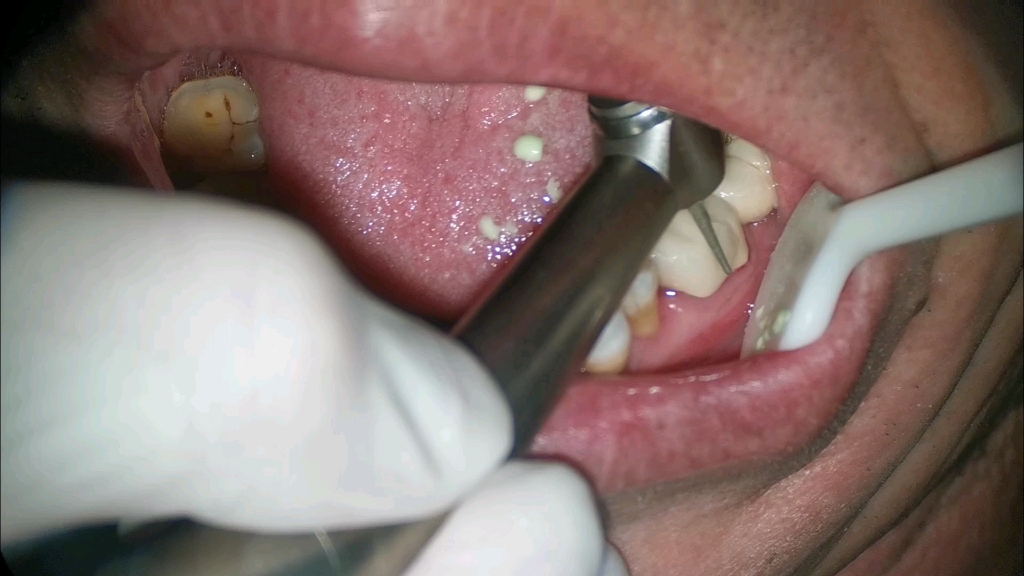

基牙腐烂的临床处理需分情况若基牙出现疼痛且修复体松动,需拆除烤瓷冠,彻底清除龋坏组织后重新修补牙体,必要时需进行桩核修复以增强固位力,最后重新制作烤瓷牙若腐烂仅限于表层且修复体稳固,可直接去除龋坏部分后充填,再评估是否需要更换修复体预防基牙腐烂的关键在于定期维护建议每612个。

1如果是黏接剂发生松解,造成烤瓷牙脱落,可以对牙冠和基牙消毒,换用新的黏接剂进行黏固2如果基牙颌龈距离过短固位力较差,需制作桩核增强固位3如果基牙发生龋坏,需去除腐质,使用玻璃离子水门汀复合树脂充填后重新牙体预备,制作新的烤瓷冠修复4如果烤瓷冠已经破损,不能隔绝唾。

如果烤瓷牙只是牙冠部分脱落,而局部的基牙上方没有任何龋坏和其他缺陷,那么可以把基牙上的粘接剂和牙冠上的粘接剂清除干净后重新粘接基牙存在折裂或龋坏如果烤瓷牙脱落后,发现局部的基牙上方存在着折裂龋坏,且这些龋坏已经无法修补,那么这颗牙齿可能无法保留,此时无法简单地将烤瓷牙重新粘接。

烤瓷牙掉出来后,可采取以下治疗措施如果烤瓷牙冠没有破损且基牙完整清除牙冠内部残留的黏接剂对牙冠进行酒精消毒应用玻璃离子水门汀等重新黏固如果基牙高度低于4mm,固位力较差进行根管治疗黏固桩核,增加颌龈高度制取印模,重新制作烤瓷牙冠修复如果烤瓷牙冠发生穿孔或崩瓷需制作新的。